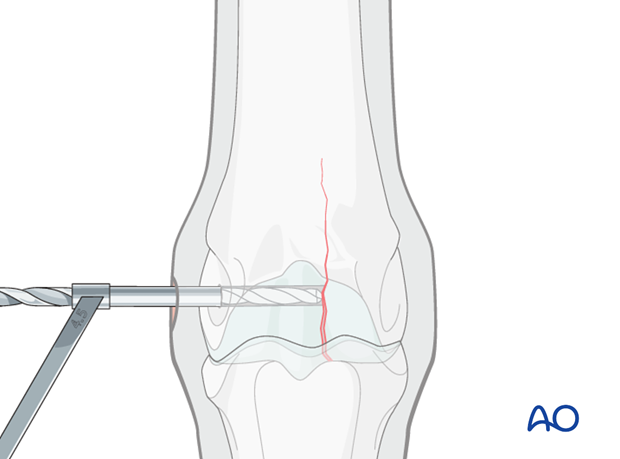

The glide hole must be drilled exactly to the fracture plane or just beyond it. It is absolutely essential in a non-displaced fracture, that the correct length and direction of the glide hole be verified with radiographs. Preoperative measurements on radiographs and careful measurements during drilling will help avoid any errors.

If generously draped, the overall alignment of the limb is easy to appreciate in a standing horse and it is actually easier to maintain correct orientation of the drill and drill bit because of this.

The 4.5 mm drill bit is removed, holding the drill guide in place. A 2.5 mm pin is placed through the drill guide into the glide hole.